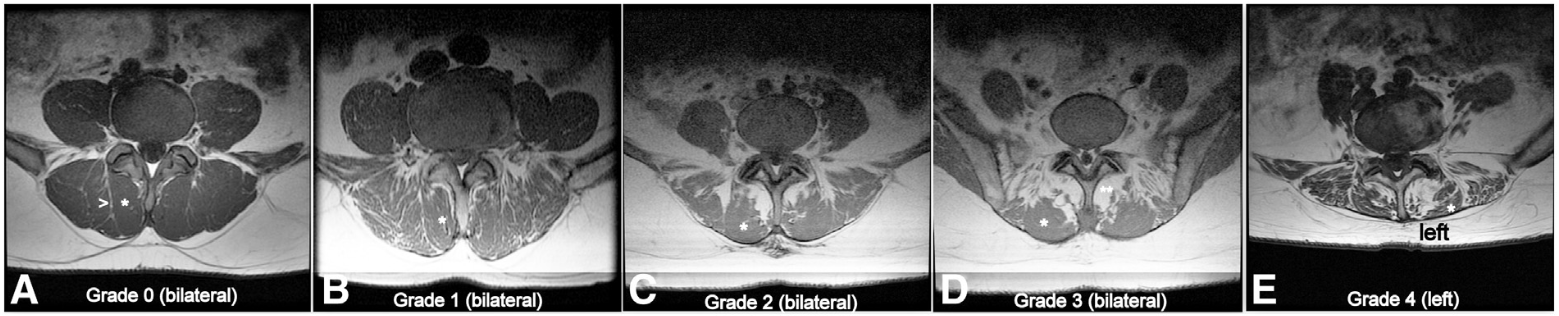

Classification de Schizas

Description de chaque catégorie :